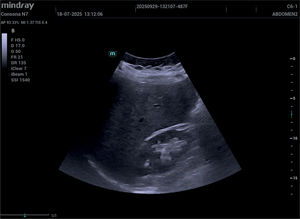

Cuando el cólico renal sigue doliendo, ¿entonces qué?